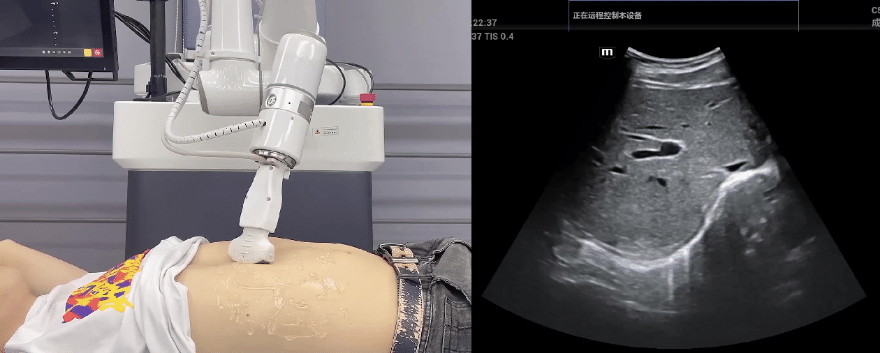

米兰·(milan)中国协作机器人搭载库柏特自主研发的机器人遥操作、多模态数据采集与处理、机器人模仿学习、机器人力位控制等技术升级变革传统超声,可实现远程+自主超声扫查与诊断,从传统远程超声仅能对话会诊变革升级为能对话、能操作,使得基层患者可就近享受异地三甲专家扫诊服务。实现专家端与患者端远程连接,并支持专家端与多路患者端自由切换控制。

EC66协作机器人末端可搭载主流品牌高品质超声仪,让操作指令和影像低延迟、高精准、高保真传输,确保检查可靠、医患放心;智能力控等三重防护系统,确保患者舒适、安全。

米兰·(milan)中国协作机器人与超声深度打通,最大程度保留医生左右手同时操作传统超声的习惯,并改善其舒适性,超声检查实际应用场景展示如下: